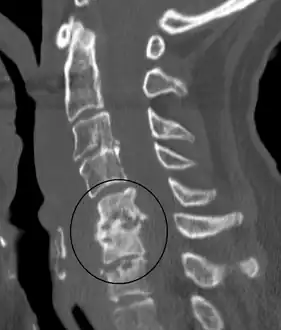

Discitis with anterior abscess (and disc space abscesses)

An infected disc at the level of C5 C6 causing neurological symptoms